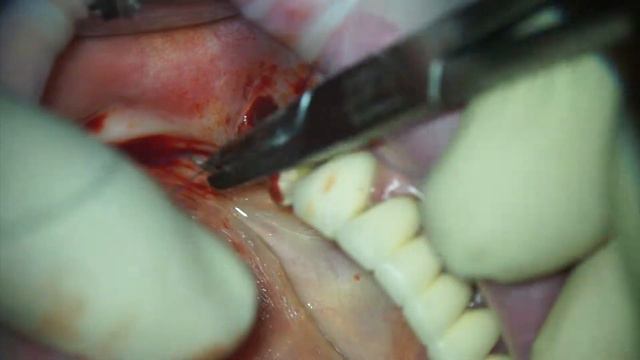

Удаление смотреть онлайн

02:40

Удаление

Семья и воспитание 16 просмотров